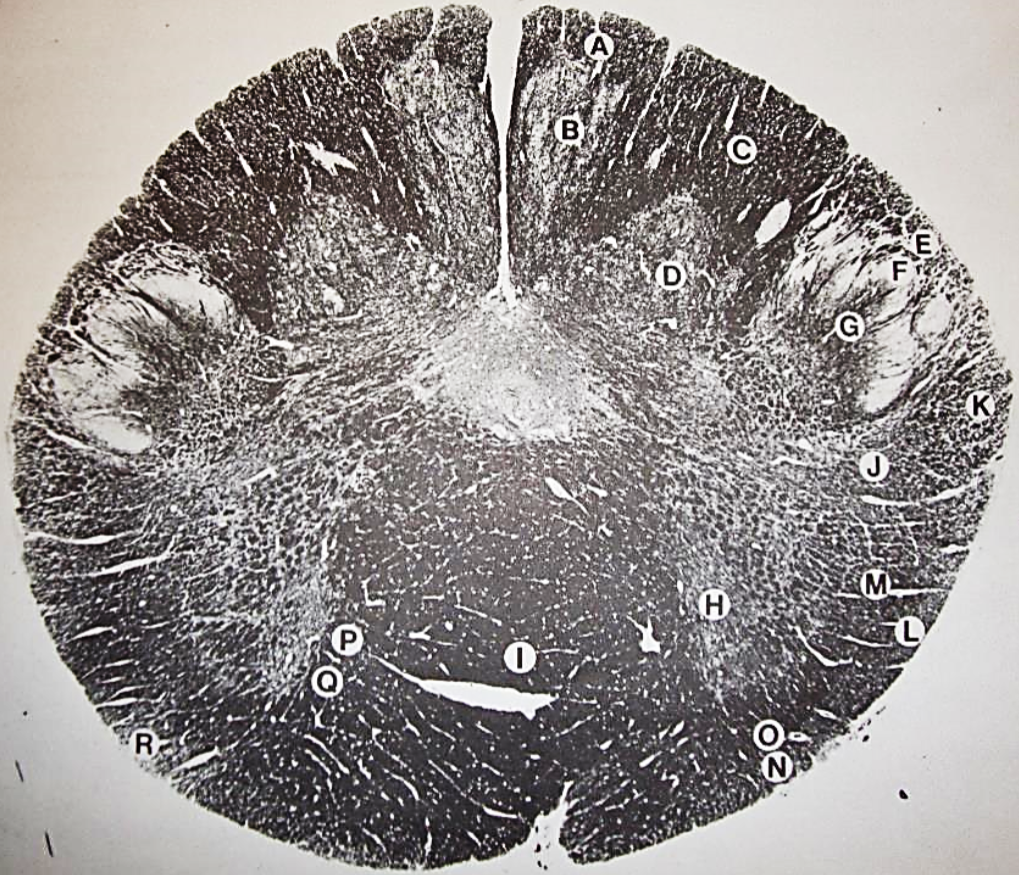

A

fasciculus gracilis

B

gracile nucleus

C

fasciculus cuneatus

D

cuneate nucleus

F

internal arcuate fibers

G

decussation of internal arcuate fibers

H

medial lemniscus

I

hypoglossal nucleus

J

dorsal motor nucleus vagus

K

solitary fasciculus

L

solitary nucleus

M

dorsal longitudinal fasciculus

N

spinal trigeminal tract

O

spinal trigeminal nucleus

P

posterior spinocerebellar tract

Q

anterior spinocerebellar tract

R

spinal lemniscus

S

lateral vestibulospinal tract

T

rubrospinal tract

U

lateral reticular nucleus

V

medial accessary olivary nucleus

W

pyramidal (corticospinal) tract

X

arcuate nucelus

Y

medial longitudinal fasciculus

Z

tectospinal tract

a

fascicles of hypoglossal nerve